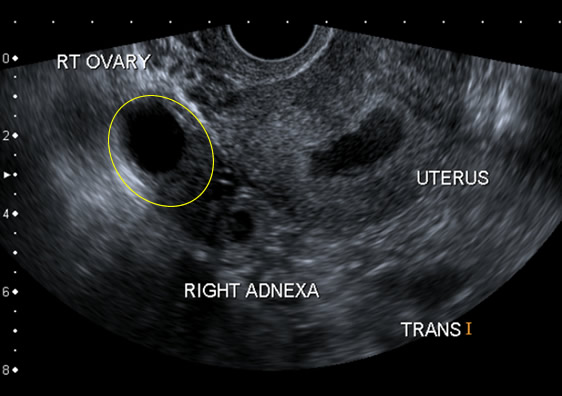

In this case of ectopic pregnancy, the ultrasound has been performed transvaginally. The details of the ultrasound are particularly well shown:

- The normal right ovary is seen

- The endometrium is thickened and there is fluid in the cavity. This has been called the pseudo-gestational sac

- The gestation sac is seen outside the uterus, next to the ovary. This is called the 'tubal ring'

| Fig 1 Transvaginal ultrasound | Zoom |